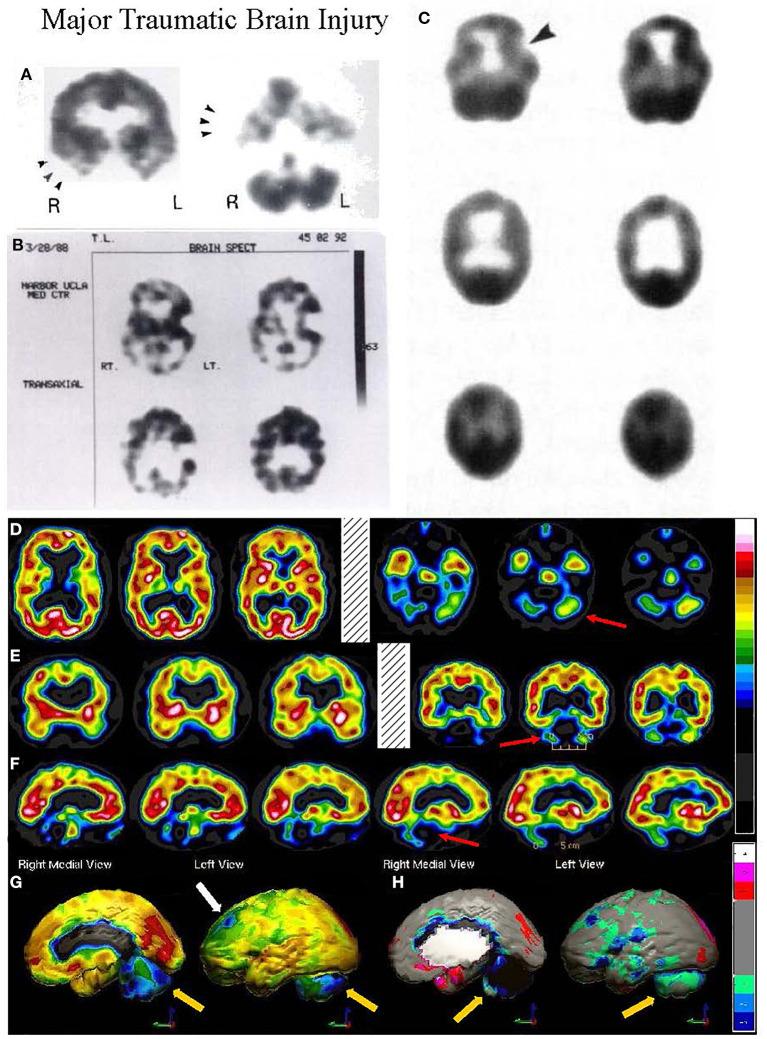

Brain perfusion single photon emission computed tomography (SPECT) scans were initially developed in 1970's. A key radiopharmaceutical, hexamethylpropyleneamine oxime (HMPAO), was originally approved in 1988, but was unstable. As a result, the quality of SPECT images varied greatly based on technique until 1993, when a method of stabilizing HMPAO was developed. In addition, most SPECT perfusion studies pre-1996 were performed on single-head gamma cameras. In 1996, the Therapeutics and Technology Assessment Subcommittee of the American Academy of Neurology (TTASAAN) issued a report regarding the use of SPECT in the evaluation of neurological disorders. Although the TTASAAN report was published in January 1996, it was approved for publication in October 1994. Consequently, the reported brain SPECT studies relied upon to derive the conclusions of the TTASAAN report largely pre-date the introduction of stabilized HMPAO. While only 12% of the studies on traumatic brain injury (TBI) in the TTASAAN report utilized stable tracers and multi-head cameras, 69 subsequent studies with more than 23,000 subjects describe the utility of perfusion SPECT scans in the evaluation of TBI. Similarly, dementia SPECT imaging has improved. Modern SPECT utilizing multi-headed gamma cameras and quantitative analysis has a sensitivity of 86% and a specificity of 89% for the diagnosis of mild to moderate Alzheimer's disease-comparable to fluorodeoxyglucose positron emission tomography. Advances also have occurred in seizure neuroimaging. Lastly, developments in SPECT imaging of neurotoxicity and neuropsychiatric disorders have been striking. At the 25-year anniversary of the publication of the TTASAAN report, it is time to re-examine the utility of perfusion SPECT brain imaging. Herein, we review studies cited by the TTASAAN report vs. current brain SPECT imaging research literature for the major indications addressed in the report, as well as for emerging indications. In Part II, we elaborate technical aspects of SPECT neuroimaging and discuss scan interpretation for the clinician.

脑灌注单光子发射计算机断层扫描(SPECT)最初是在20世纪70年代开发的。一种关键的放射性药物,六甲基丙烯胺肟(HMPAO),最初于1988年获批,但不稳定。因此,直到1993年开发出一种稳定HMPAO的方法之前,SPECT图像的质量因技术不同而有很大差异。此外,1996年以前的大多数SPECT灌注研究是在单头伽马相机上进行的。1996年,美国神经病学学会治疗与技术评估小组委员会(TTASAAN)发布了一份关于SPECT在神经系统疾病评估中应用的报告。尽管TTASAAN报告于1996年1月发表,但它于1994年10月被批准发表。因此,TTASAAN报告中用于得出结论的脑SPECT研究大多早于稳定HMPAO的引入时间。虽然TTASAAN报告中关于创伤性脑损伤(TBI)的研究只有12%使用了稳定示踪剂和多头相机,但随后有69项研究涉及超过23000名受试者,描述了灌注SPECT扫描在TBI评估中的效用。同样,痴呆症的SPECT成像也有所改进。利用多头伽马相机和定量分析的现代SPECT对轻度至中度阿尔茨海默病诊断的敏感性为86%,特异性为89%,与氟脱氧葡萄糖正电子发射断层扫描相当。癫痫神经成像也取得了进展。最后,神经毒性和神经精神疾病的SPECT成像发展显著。在TTASAAN报告发表25周年之际,是时候重新审视灌注SPECT脑成像的效用了。在此,我们回顾了TTASAAN报告引用的研究与当前脑SPECT成像研究文献,涉及该报告中讨论的主要适应症以及新出现的适应症。在第二部分中,我们详细阐述了SPECT神经成像的技术方面,并讨论了临床医生对扫描结果的解读。